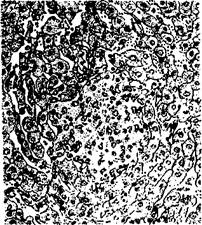

Рисунок: эндофлебит, гистосрез печени теленка.

Рисунок: некротический очажок, окруженный лимфоидными клетками в печени теленка (окраска гематоксилин-эозином)